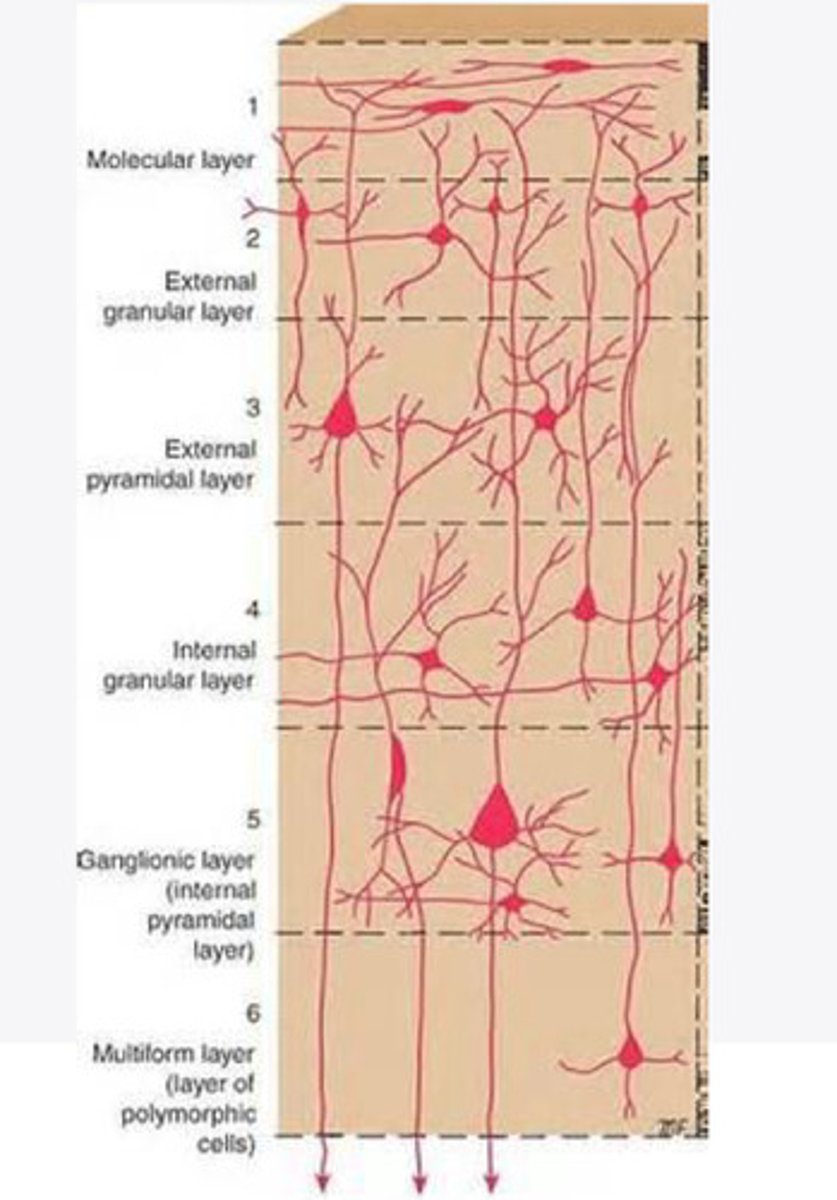

divided into 6 distinct layers, due to varying densities of cell body types within each layer

The cortex of the brain is divided into how many layers? Why is it divided into layers?

Layers of the cortex of the brain pic

2 and 4

What are the layers of the cortex that are associated with input?

3 and 5

What are the layers of the cortex that are associated with output?

molecular layer

What is the name of Layer 1 of the cortex of the brain?

very few cells

Does Layer 1 of the cortex have a lot or few cells?

receives dendrites from internal layers so it may actually function as a coordinating center where layers can communicate action

What does Layer 1 of the cortex do?

1

Every layer sends densities to Layer ____?

1

What layer serves as the "water cooler" of the brain?

external granular layer

What is the name for layer 2 of the cortex of the brain?

receives input from other cortical regions

What is the function of Layer 2 of the Cortex of the brain?

Stellate

What type of cells (stellate/pyramidal) would be most concentrated in Layer 2?

external pyramidal layer

What is the name for layer 3 of the cortex of the brain?

sends output to the other cortical layers

What is the function of Layer 3 of the cortex of the brain?

pyramidal

What type of cells (stellate/pyramidal) would be most concentrated in Layer 3 of the brain?

Layers 2 and 3

What layers are associated with association and commissural fibers?

Layer 3 - axons of cell bodies

Layer 2 - synapse into target areas in Layer 2

What part of the axons is in Layer 2/ in layer 3?

Layer 3 - external pyramidal layer

All axonal cel bodies for association and commissural fibers lie within what layer of the Cortex of the brain?

internal granular

** or called the striate cortex because it is so thick that you can see a line through this layer even in unstrained brain slides

What is the name for the 4th layer of the cortex of the brain?

receives input from the thalamus, geniculocortical layer, and other brainstem areas

What is the function for the 4th layer of the Cortex of the brain?

very thick within the vision, auditory, and somatosensory areas

Is Layer 4 thick or thin within SENSORY areas of the cortex?

Internal pyramidal

What is the name for Layer 5 of the cortex of the brain?

sends axons to the brainstem (corticobulbar) and spinal cord (corticospinal)

What is the function of Layer 5 of the cortex of the brain?

in motor areas of the cortex?

Where is layer 5 very thick in the brain?

the frontal lobe -- very motor heavy

What lobe of the brain will have a thick layer 5 of the cortex of the brain?

the multiform layer

What is the name of layer 6 of the cortex of the brain?

-sends axons back to the thalamus through corticogeniculate fibers

-modulates what information the thalamus sends to the cortex to control the strength of the signal received and modulate what you pay attention to

What is the function of layer 6 of the cortex of the brain?

no

Is layer 6 a motor layer?